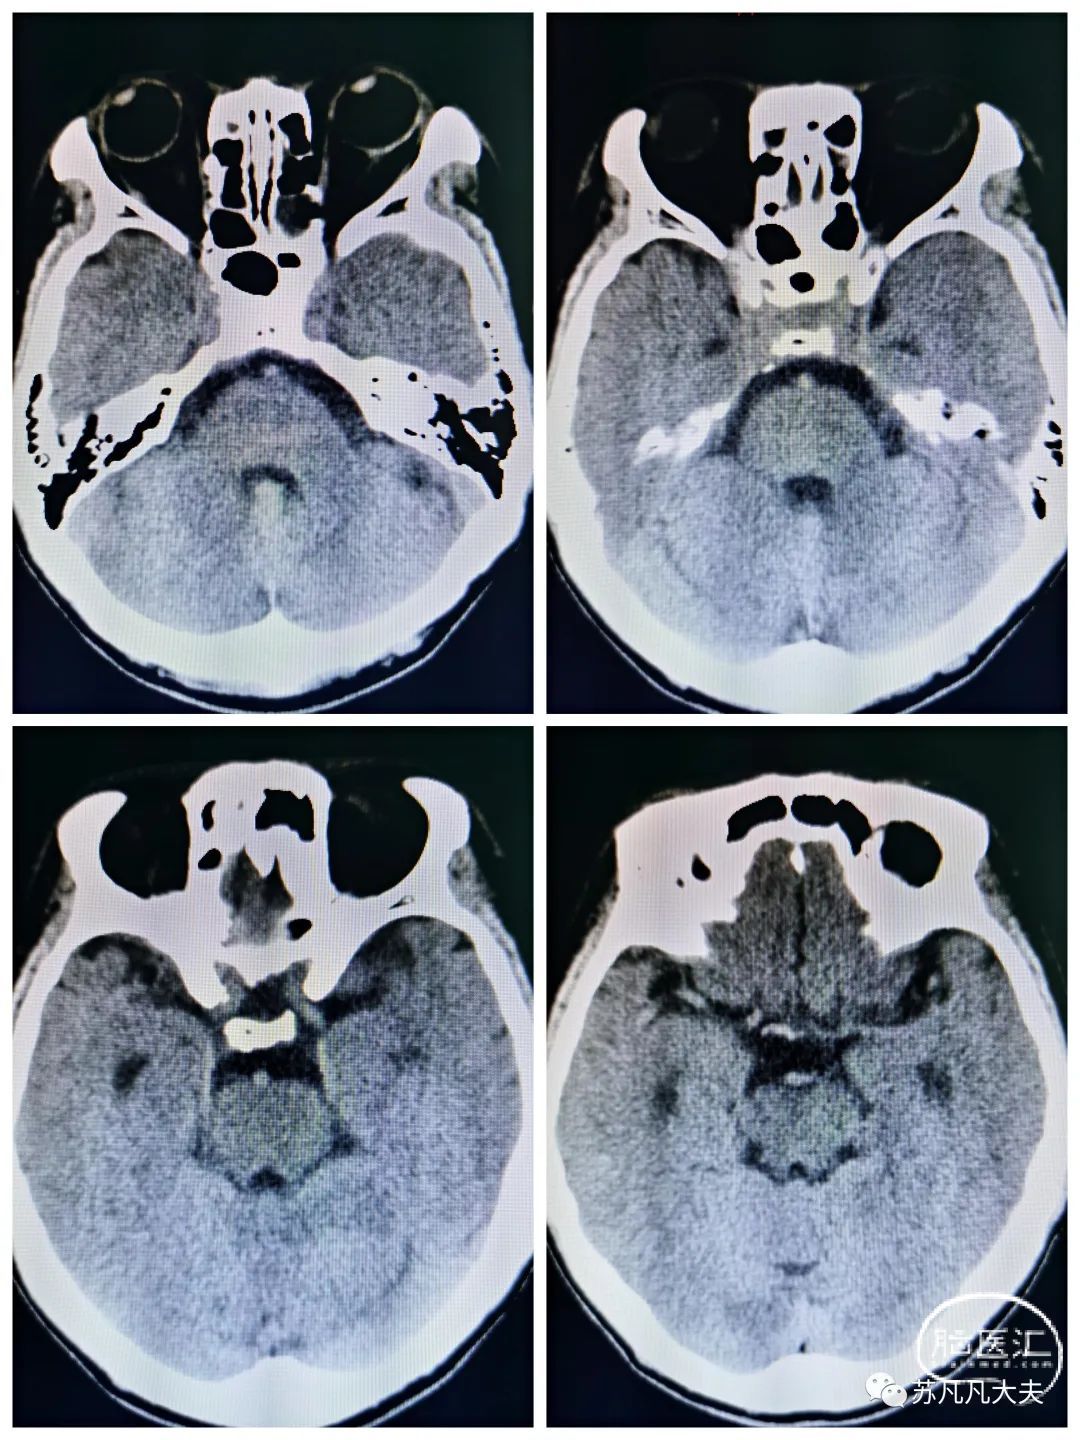

头CT可见双侧小脑梗死灶(11:33)

核磁DWI示双侧小脑,右侧颞叶,岛叶,双侧顶枕叶多发脑梗死。(19:30)